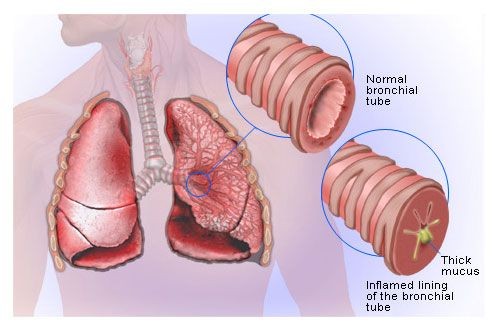

What Is Bronchitis?

Bronchitis is when the tubes that carry air to your lungs, called the bronchial tubes, get inflamed and swollen. You end up with a nagging cough and mucus.